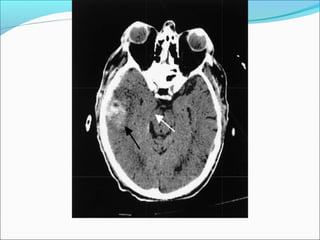

SUBARACHNOID HEMORRAGE

ļ‚—Can originate from direct vessel injury, contused cortex

or intraventricular hemorrhage.

ļ‚—In contrast to aneurysmal SAH, the blood is superficial in

the cortex and not present in the basal cisterns.

ļ‚—Usually focal (but diffuse from aneurysm)

ļ‚—In some instances, for example, if blood is found in the

sylvian fissure, a vascular study (CTA,DSA) is needed to

rule out an aneurysm rupture.

ļ‚—Can lead to communicating hydrocephalus

Intraventricular hemorrhage

ļ‚—Most commonly due to rupture of subependymal

vessels

ļ‚—Can occur from reflux of SAH or contiguous

extension of an intracerebral hemorrhage

ļ‚—Look for blood-cerebrospinal fluid level in occipital

horns